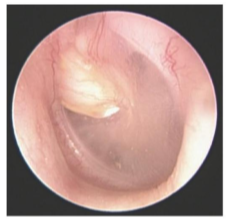

Cholesteatoma

Cyst of sqamous eputhelium usually in the ME or mastoid

Acquired cholesteatoma

Formed by retraction of TM and skin

congenital cholesteatoma

Caused by ETD and OM; causes CHL